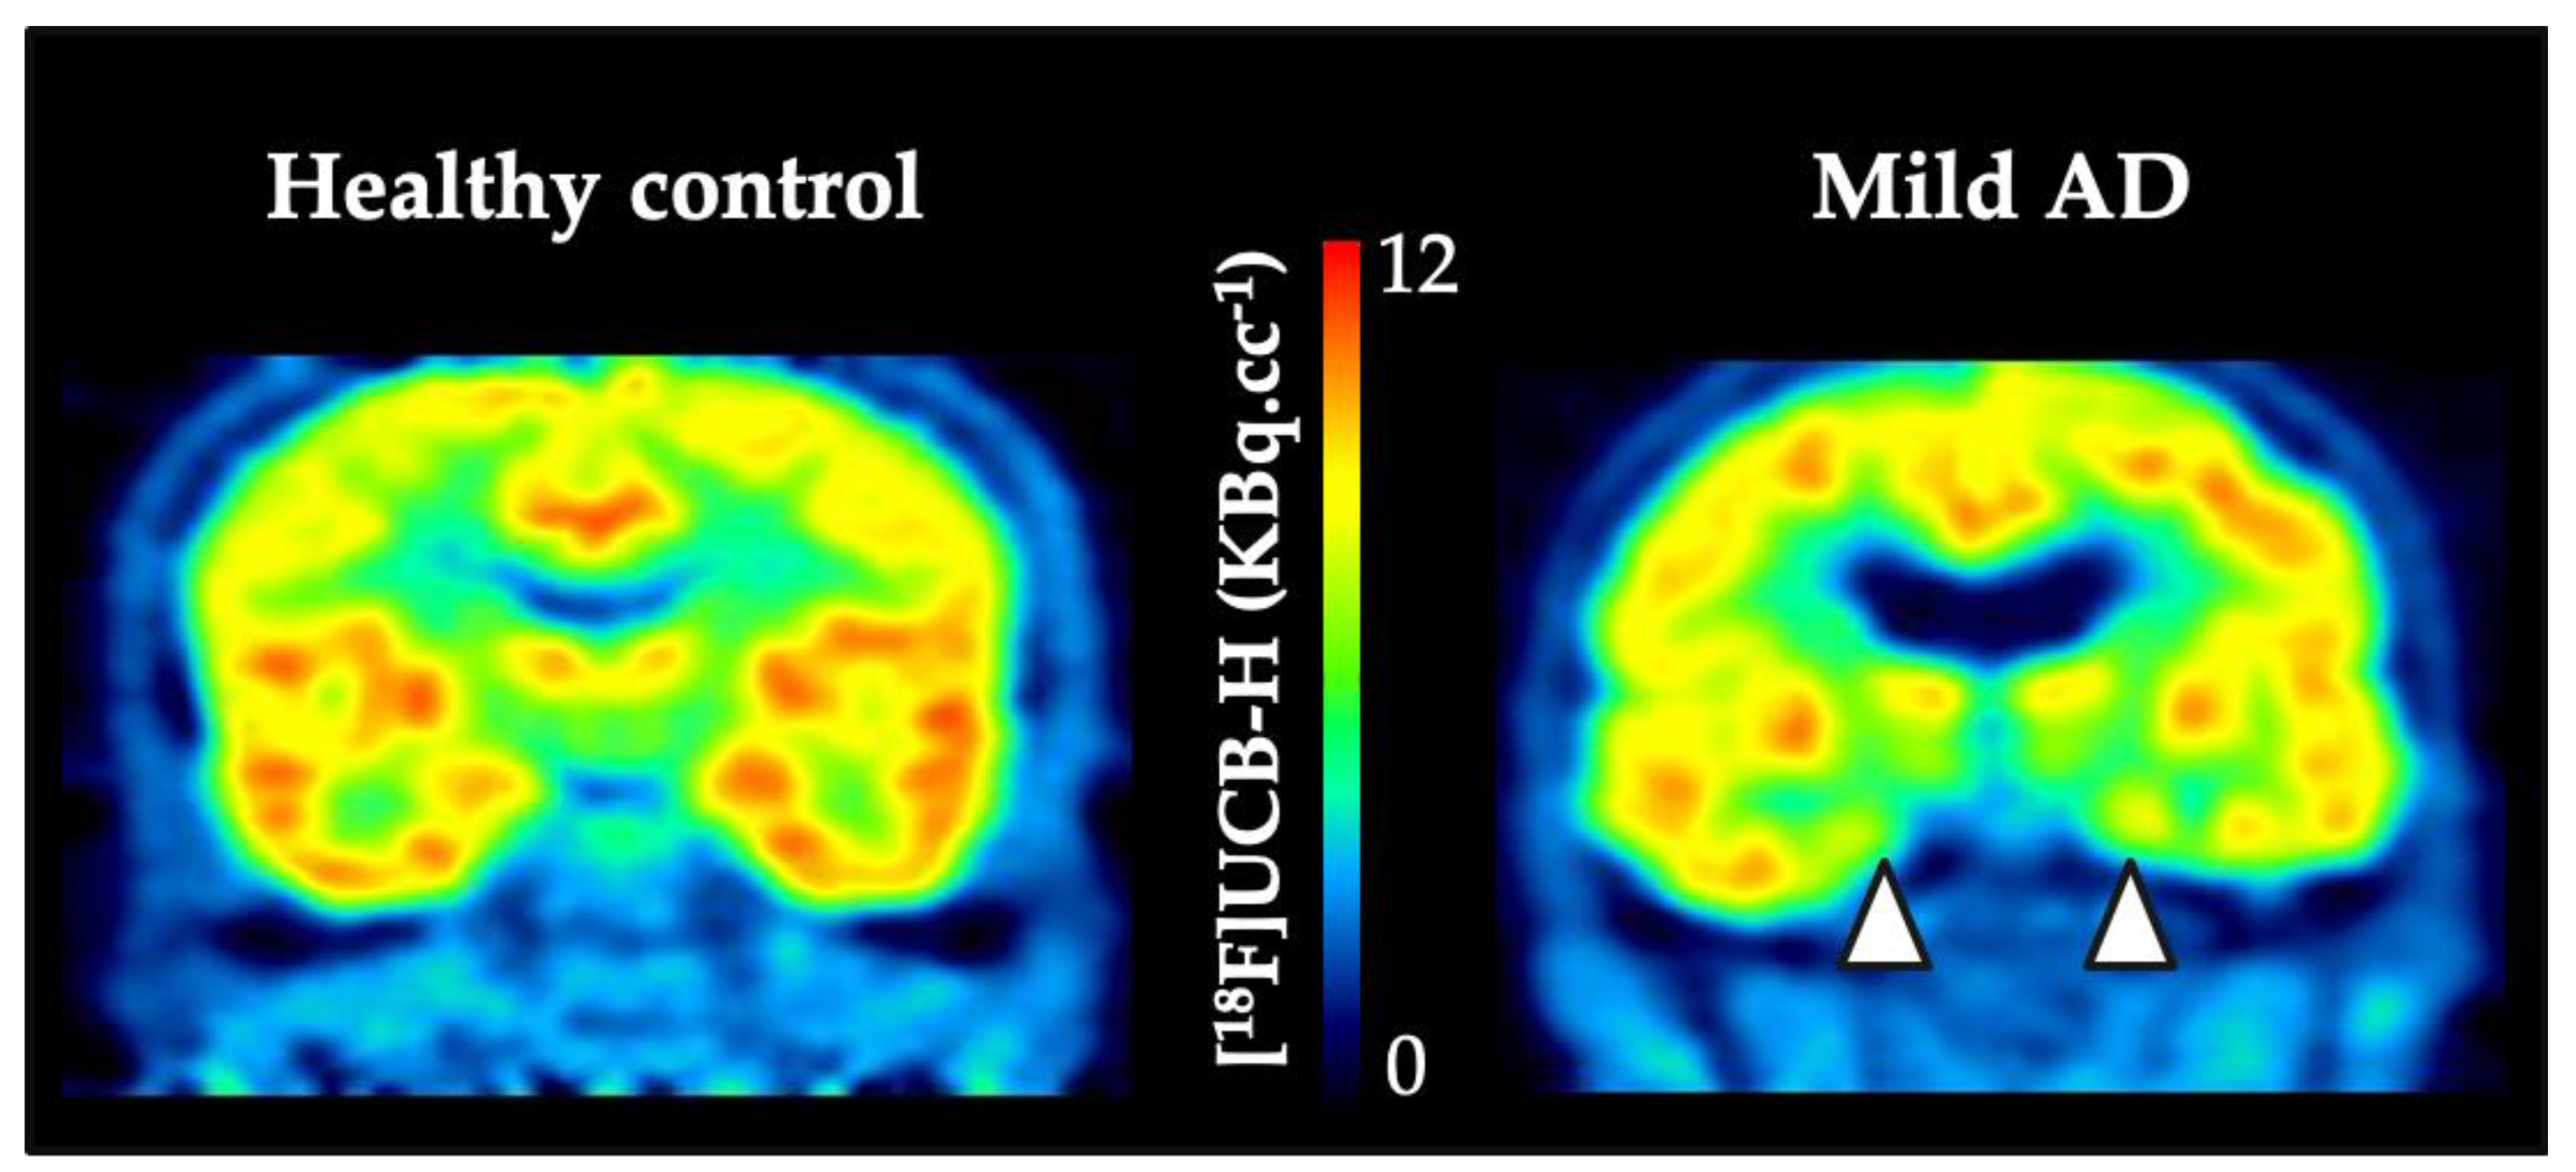

- Bastin, C.; Bahri, M.A.; Meyer, F.; Manard, M.; Delhaye, E.; Plenevaux, A.; Becker, G.; Seret, A.; Mella, C.; Giacomelli, F.; et al. In vivo imaging of synaptic loss in Alzheimer’s disease with [18F]UCB-H positron emission tomography. Eur. J. Nucl. Med. Mol. Imaging 2019, 47, 390–402. [Google Scholar] [CrossRef]